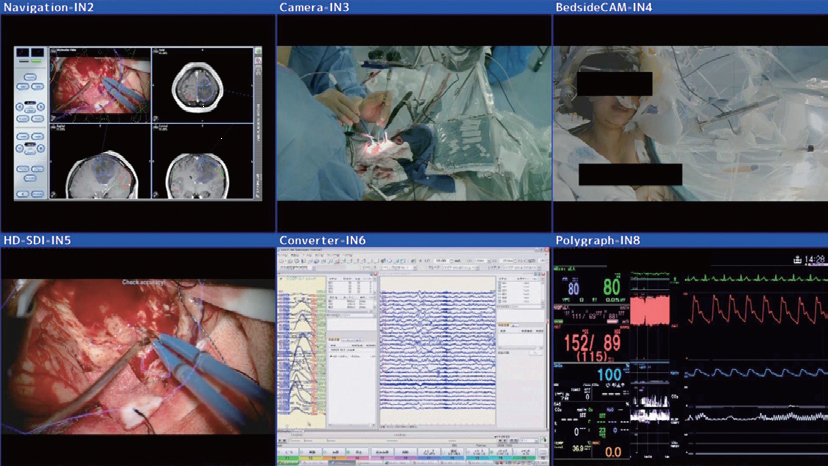

脳神経外科手術を支える最新技術には、電気生理学的モニタリング、ナビゲーション、Functional MRI、Tractography、3次元構築画像解析、術中MRI、術中CT、覚醒下手術、血管内治療、ハイブリット手術などがあり、多数の画像情報が生まれる。

手術用大型モニタの特徴は、基本的には画像の高精度化・大型化である。情報信号配信マネージャーは、マルチレイアウトで手術中に手技に応じて必要となる各種画像を自由なフレームサイズで術者に提示できる(図2)。さらに、大型モニタを介して各種の情報をスタッフが共有できる。

臨床的意義は、手術の精度、安全性の向上である。手術手技の正確性、安全性の向上や、覚醒下手術における手術顕微鏡、脳波計、患者モニタカメラ、ナビゲーション、生体情報、術中MRI画像などの多くの情報を手術用大型モニタに統合して術者に提示することで、神経障害を来さずに腫瘍を摘出できる。麻酔科医やコメディカルが同じモニタで情報を共有し手術に参加することで、スタッフ全体の意識が変わる。